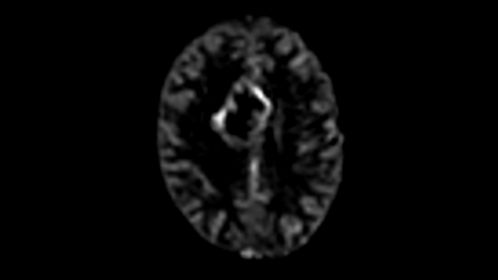

*pCASL (pseudo-Continuous Arterial Spin Labeling) ermöglicht die Darstellung der zerebralen Perfusion und funktionellen Physiologie auf kontrastfreie Weise mit geringer Verzerrung* und unter Abdeckung des gesamten Gehirns.